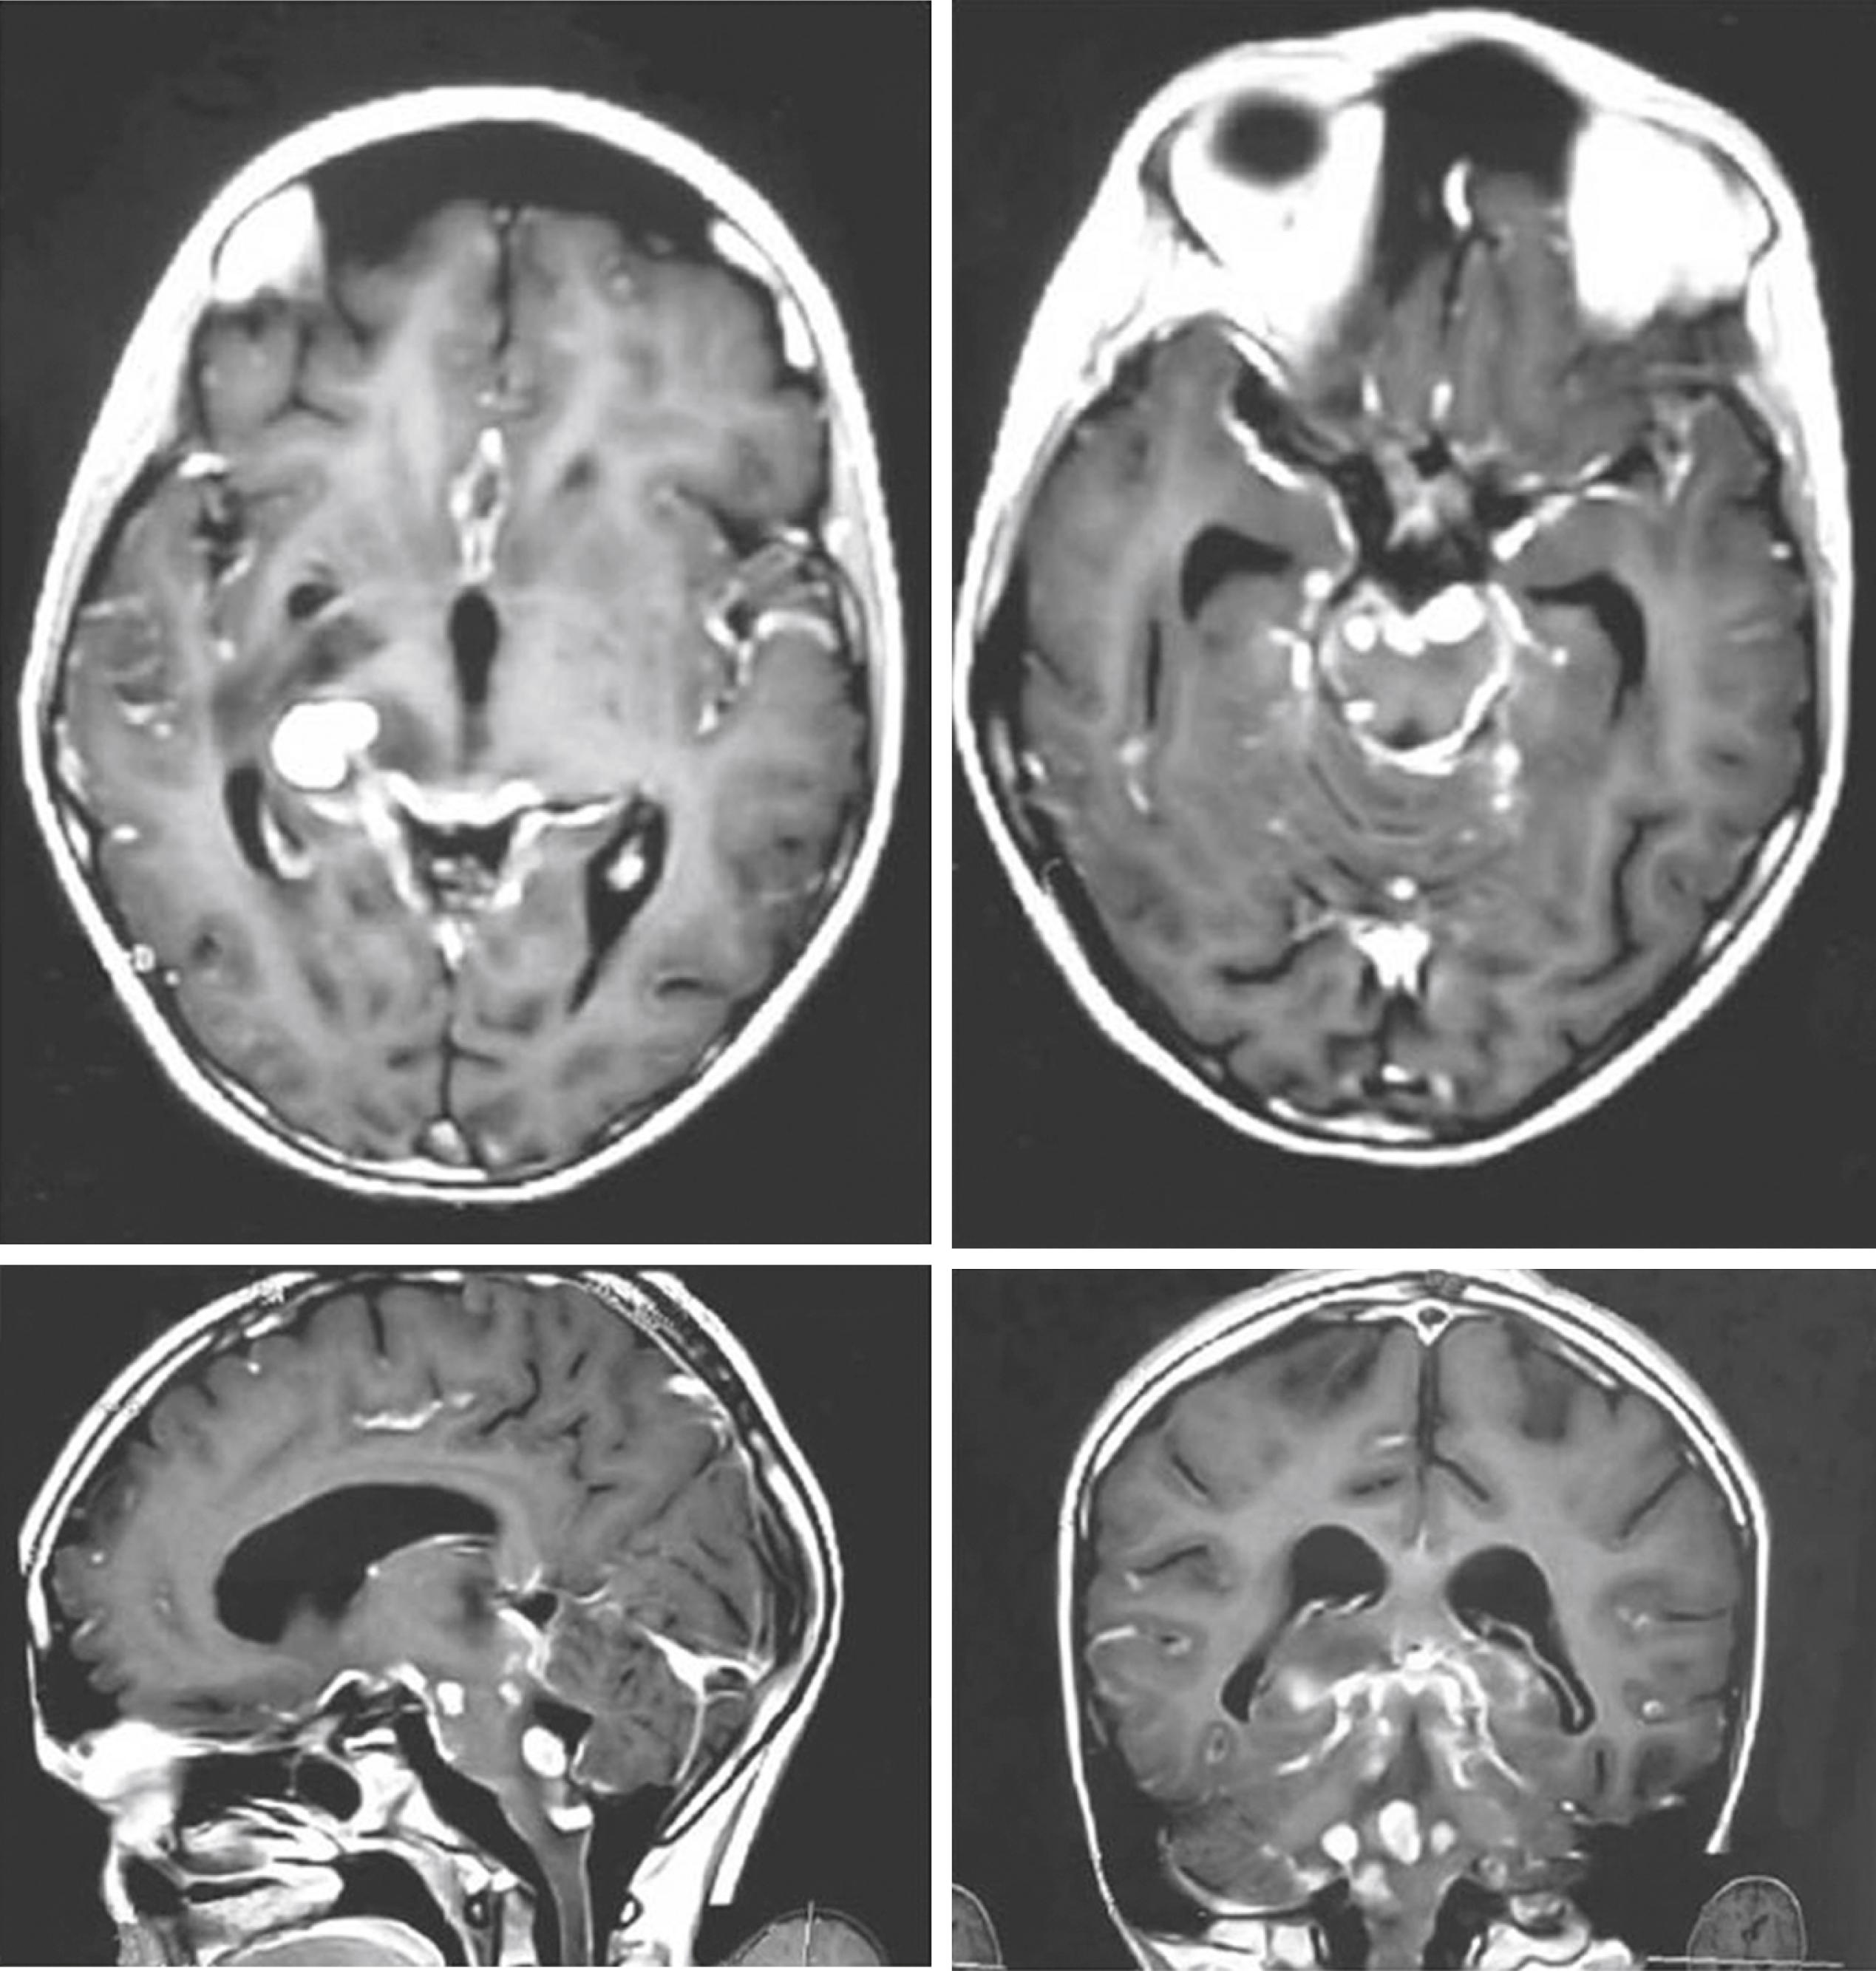

Magnetic resonance imaging (MRI) is more sensitive than computed tomography (CT) for early detection of infarcts, meningeal and parenchymal disease ( Fig. 132.3 ). Superior to routine imaging, magnetization transfer (MT) imaging demonstrates abnormal meninges as hyperintense on precontrast MTT1 images which further enhances on postcontrast T1 weighted MT images. In addition, MT ratio (MTR) quantification helps in predicting the etiology of meningitis. , Visibility of the inflamed meninges on precontrast MTT1 images with low MTR is fairly specific of TBM, which differentiates it from other nontuberculous chronic meningitis.

FIGURE 132.3, Gadolinium–diethylene triamine penta-acetic acid–enhanced T1-weighted axial, sagittal, and coronal images demonstrate enhancement of the leptomeninges over the surface of the brain. There are also multiple tubercles studding the brain parenchyma.